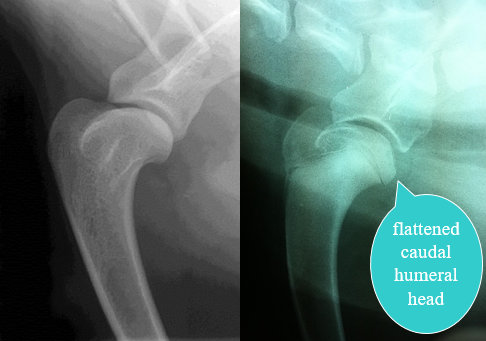

What radiographic findings are compatible with OCD?

Flattening contour of the joint